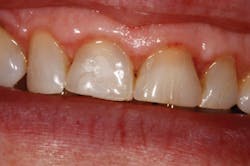

This patient came directly out of hygiene with a chipped tooth. The patient was aware that teeth Nos. 7-10 were in need of crowns. Tooth No. 8 was bonded (figure 1). The patient was informed that this was a temporary fix and agreed to schedule crowns for teeth Nos. 8 and 9. Due to wear, secondary to bruxism, teeth Nos. 8 and 9 had supererupted, bringing their gingival margins too far coronal for proper esthetics. A preprosthetic esthetic crown lengthening was suggested to ensure optimal esthetics. Orthodontic intrusion was also considered, but the patient was not interested. A mock-up of the results in gingival margin improvement was demonstrated with flowable composite. The patient preferred this option to surgery with a periodontist, which would have included a flap and four to six sutures. Soft tissue and approximately 2 mm of bone needed to be removed in order to reestablish proper gingival levels. This was an unscheduled case; the patient came right out of hygiene and requested to complete the crown lengthening procedure while she was in the office. She just wanted to be sure that it was still okay to meet her friend for lunch (it was, and she had sesame chicken).

Figure 1: Pre-op